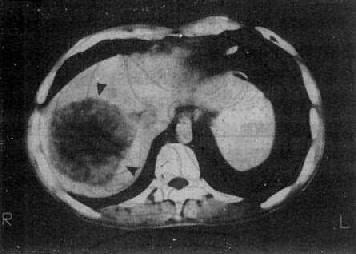

1.原发性肝癌 CT平扫绝大多数是低密度病灶,少数可以是低密度、等密度与高密度混合的病灶。肿瘤可以是单个或多个结节,也可呈巨块状。较大肿瘤因出血、坏死和囊变而致密度不均匀,中心部常出现更低密度区,其边缘部呈结节状。肿瘤边界多不清,少数边界清楚并有包膜。增强扫描肝癌区略有增强或不增强,而正常肝增强,因而使肿瘤境界更为清楚。癌变区可出现密度稍高的结节或隔,但其增强程度多不如正常肝。动态扫描时,即快速静脉注射造影剂并于开始注射后15~25秒内即行扫描,由于肝癌由肝动脉供血且供血丰富而迅速,而造影剂尚未到达肝内门静脉形成实质期,故肝癌结节可成为高密度,甚或显出高密度的异常肿瘤血管。但肝癌增强的时间较短暂,2~3分钟内即恢复为原来的低密度状态(图4-3-5)

图4-3-5 原发性肝癌

CT增强扫描,肝右叶有一较大圆形低密度肿块(↓),其边缘

部可见多个较密度的强化结节,其强化程度不如正常肝,中

心部仍为未强化的低密度区